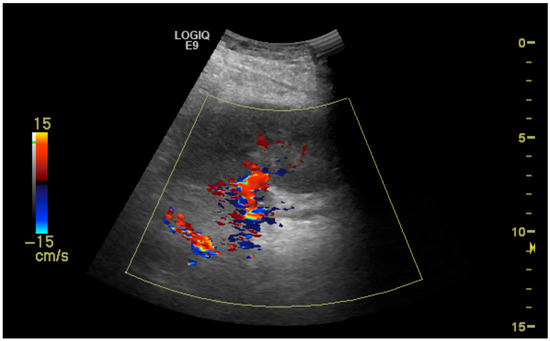

Clinical Utility of Duplex Ultrasonography in the Recognition of Transplant Renal Artery Stenosis: A Single Center Experience

2. Methods and Materials

- More than 50% renal artery stenosis on initial Duplex ultrasonography;